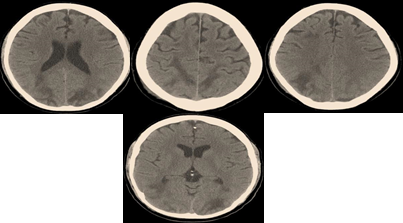

Brain imaging via computed tomography showed bilateral, symmetrical, diffuse hemispheric edema; primarily involving the parietal and occipital regions of the brain; Figure 2. The diagnosis of Posterior Reversible Encephalopathy Syndrome secondary to hypertension, sickling crisis and fluid overload was made, and treatment was initiated with the above-outlined therapy.

Figure 2

|

Figure 2 Showing CT-Brain Imaging with Extensive, Bilateral, Symmetrical Parieto-Occipital Hypo-Attenuating Lesions; Resembling Diffuse Vascular Edema of the Brain Tissue |